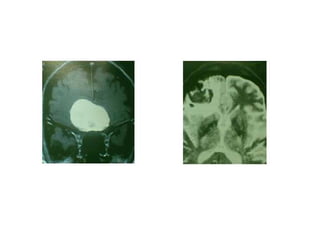

Adénome à prolactine de la glande hypophysaire.

L’épistaxis est rarement révélatrice d’un adénome hypophysaire.

Il s’agit surtout de manifestations d’une hyperprolactinémie: galactorrhée et

hypogonadisme.

Selon l’extension de la tumeur on obtient une symptomatologie supra sellaire:

céphalées et troubles visuels par compression du chiasma optique.

TRAITEMENT:

-bromocryptine

-chirurgie selle turcique par voie endoscopique